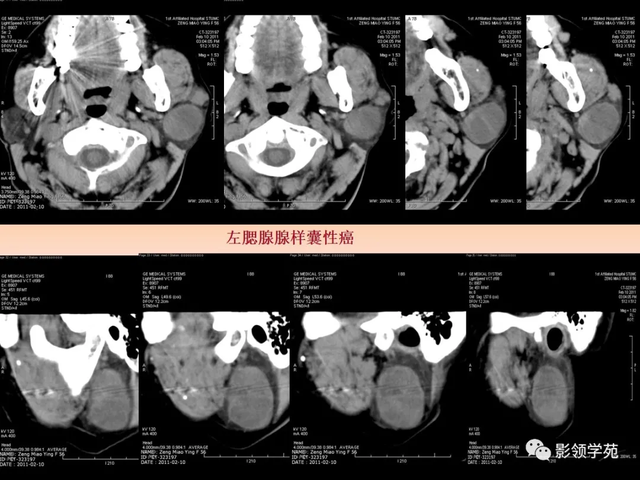

图6 a 、b 、c 囊腺癌 左侧腮腺弥漫性增大,密度增高,边缘无法确定,同侧颈部可见淋投合肿大坏死,胸锁乳突肌受侵占